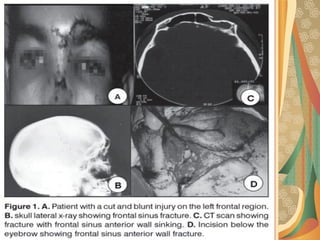

383803/12/1703/12/17 Dr YounasDr Younas

Radiopaque mass in the sinusRadiopaque mass in the sinus